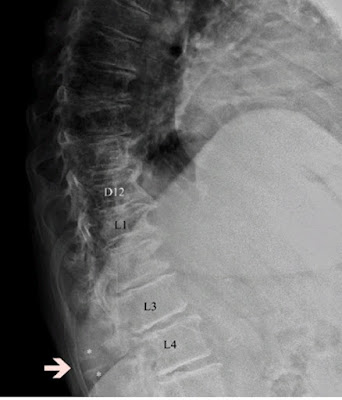

- Espondilosis. se refiere a un proceso degenerativo que afecta a los discos intervertebrales y las vértebras, lo que puede llevar a una disminución en la altura del disco y a la aparición de osteofitos (crecimientos óseos) en las vértebras. Figura 1

Figura 1. Espondilosis lumbar. Cambios discovertebrales con osteofitos anteriores (círculos).

Fuente: ver aquí